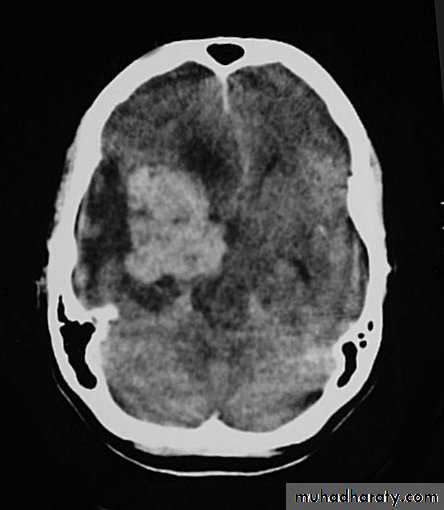

Malignant GliomaPre contrast CT

Malignant Glioma Post contrast CT